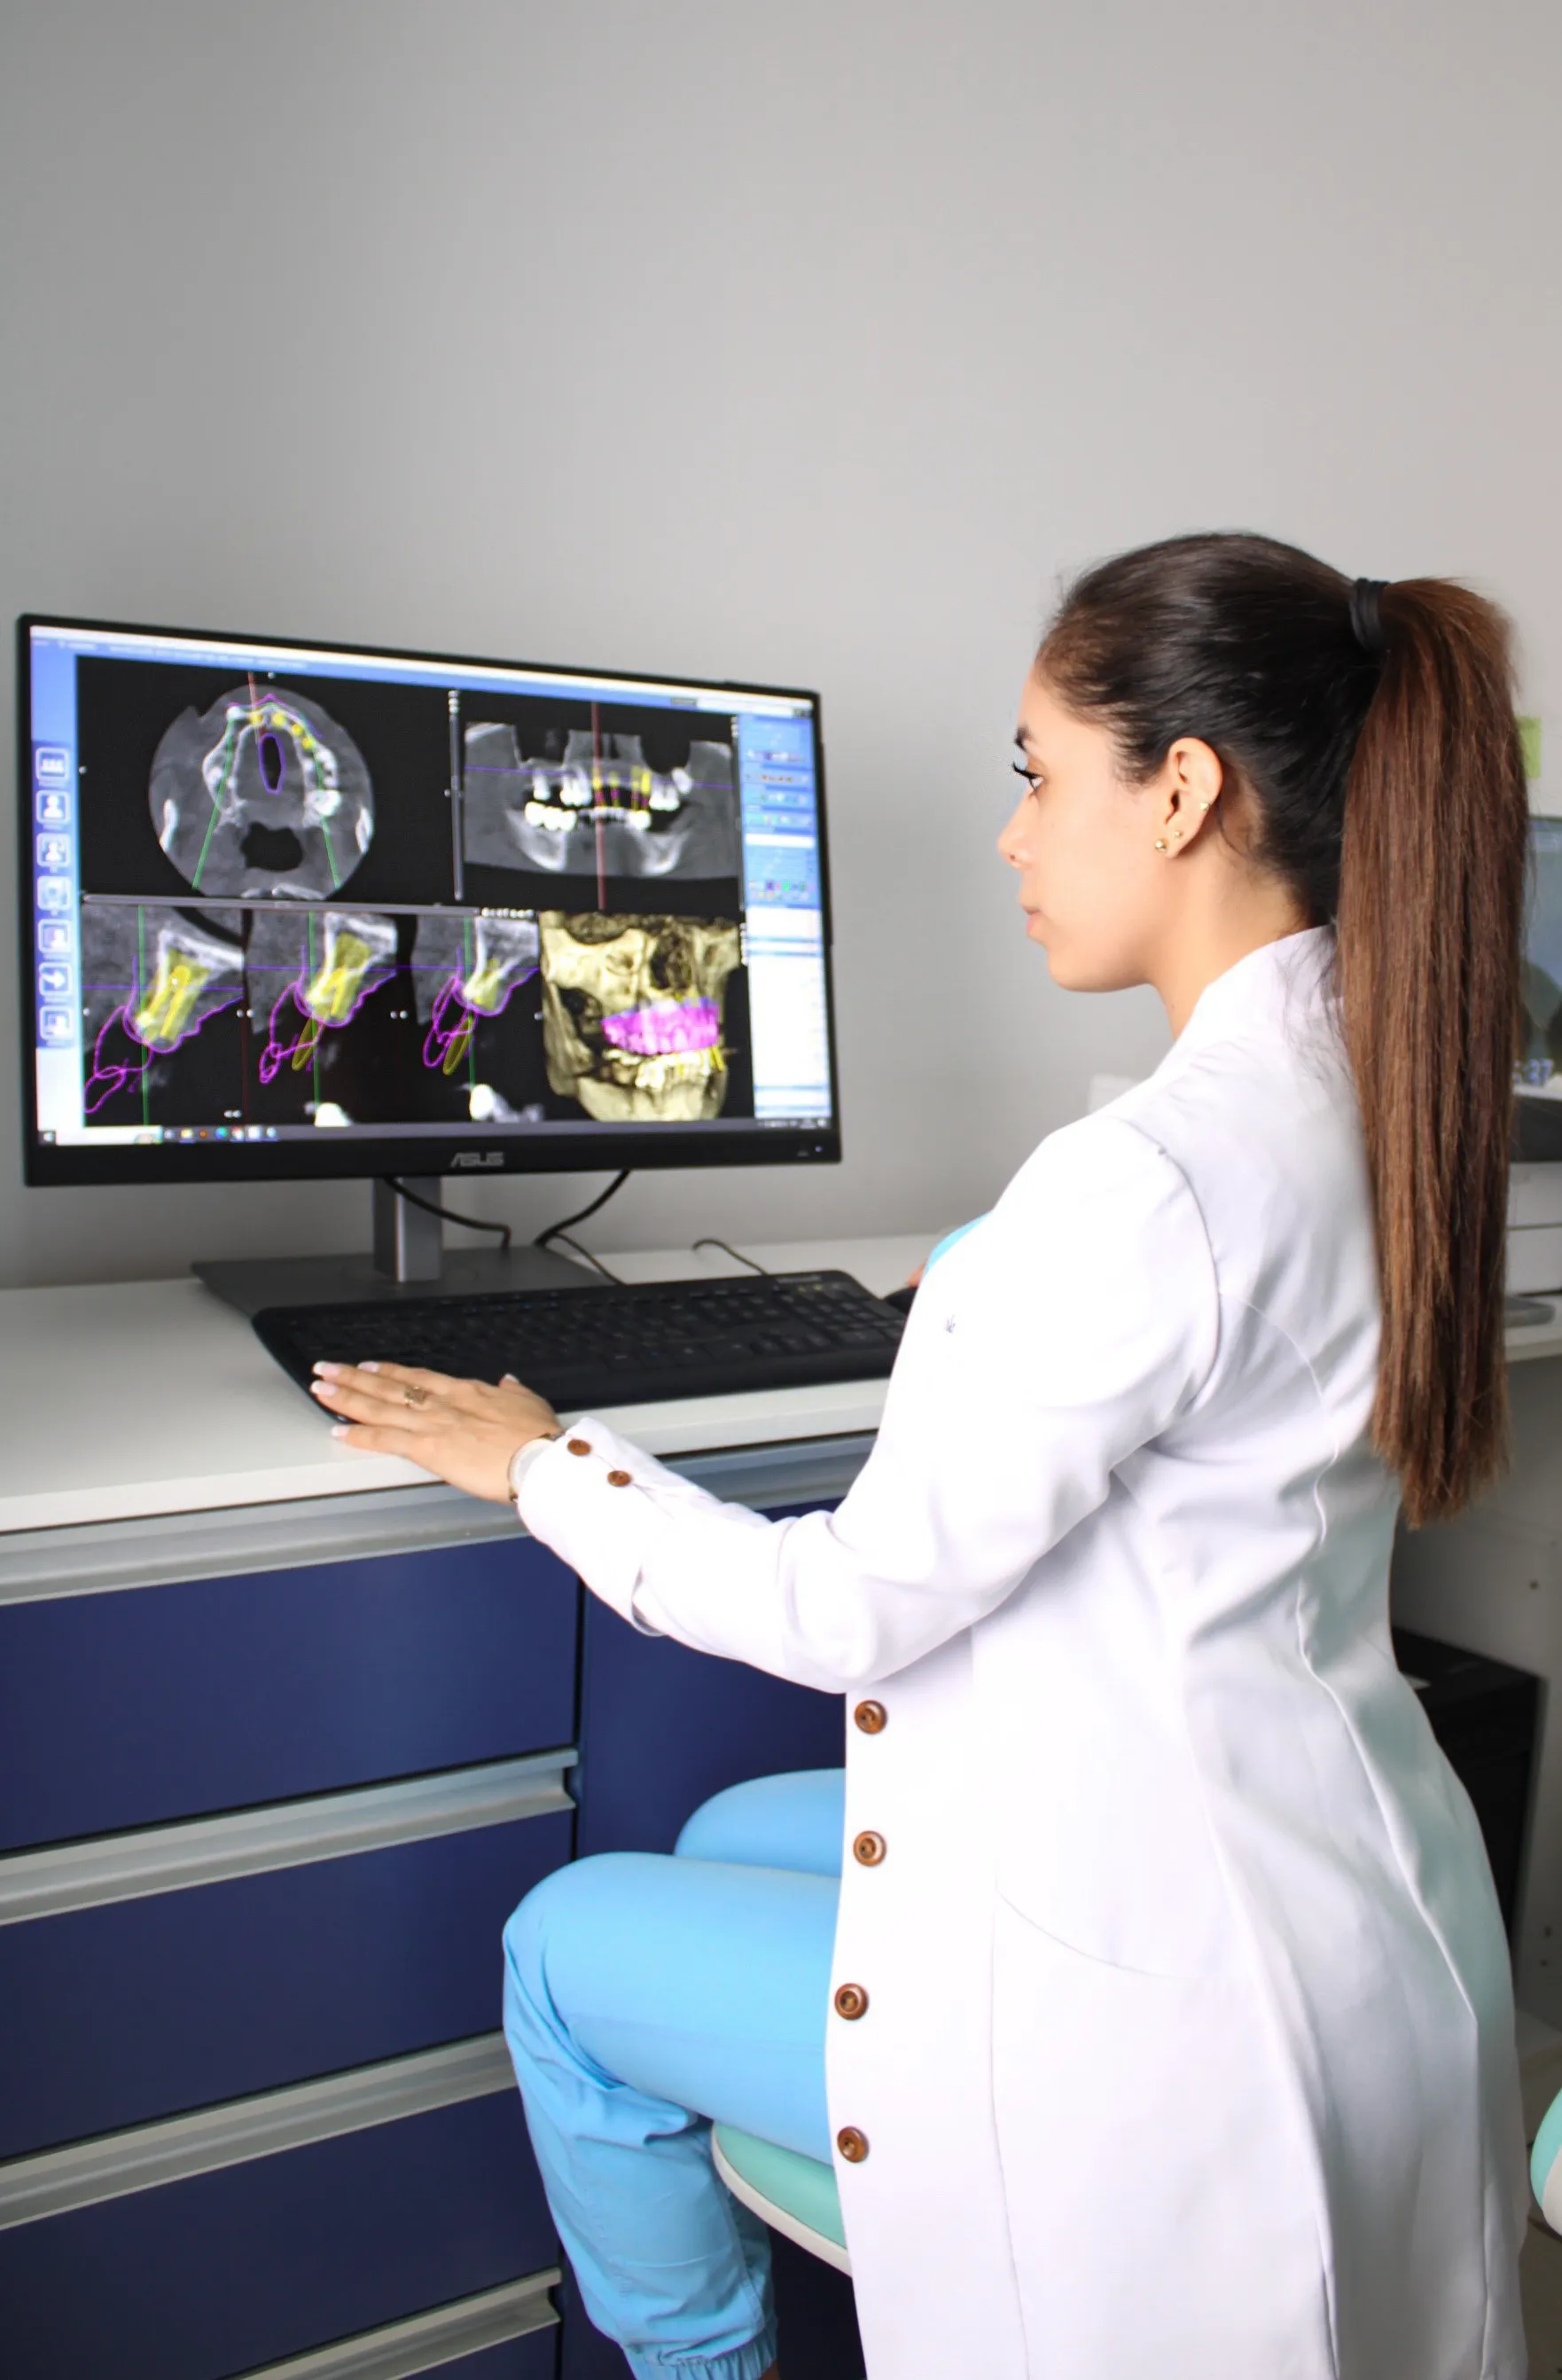

El diagnóstico es la base de todo tratamiento odontológico y para mayor precisión es fundamental que vaya acompañado de exámenes imagenológicos. Hoy en día, existen muchos tipos de rayos X y otros métodos de imágenes disponibles que pueden usarse para detectar enfermedades y anomalías bucales como cáncer bucal, caries, estructuras dentales ocultas y pérdida ósea.

Es por eso que El Centro Imagenológico Maxilofacial Clarity cuenta con el equipamiento de la más alta tecnología y profesionales especialistas en radiología que ofrecen servicios precisos y con la mejor calidad.

Planificamos todos nuestros casos con la máxima precisión y comunicación con cada doctor.

Nuestros especialistas hacen uso de sistemas de radiología digital de última generación para proporcionarle análisis de ortodoncia y cefalometría de la más alta calidad. Contamos con más de 30 análisis cefalométricos.